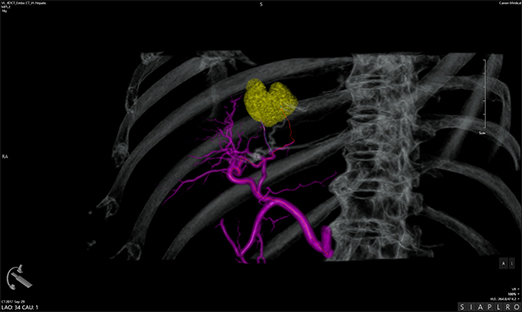

Програмне забезпечення Embolization Plan використовується для аналізу 3D-зображень. Це дозволяє виокремити пухлину і судини, що кровопостачають її, та візуалізувати для процедури трансрадіальної хіміоемболізації (TACE):